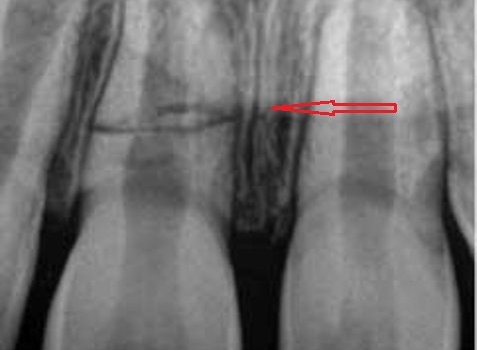

Daimi dişlərin travmatik zədələnmələri uşaq və yeniyetməlik dövründə olan şəxslərdə çox tez-tez rast gəlinir. Tac qırılmaları və lüksasiya travmalar içərisində ən çox rast gəlinənlərdir. Ancaq müxtəlif kliniki hallarda digər zədələnmə formaları da aşkar edilə bilir.

Doğru diaqnostika, müalicə planlaması və sonrakı dönəmdə izləmə uğurlu müalicəyə aparan ən başlıca faktorlardır. Diş travmaları və yaralanmaları tək diş bölgəsini əhatə edən məhdud, eyni zamanda çoxsaylı diş bölgəsini və çənənin alveol darağını əhatə edəcək qədər yayılmış formada rast gəlinə bilir. Çoxsaylı diş zədələnmələrində çox zaman fərqli dişlərdə fərqli növ zədələnmə şəkili aşkar edilə bilir ki, bu da hər bir dişə individual yanaşma və müalicə metodu tələb edir.

Bu tip zədələnmələrin bu sahədə təcrübəsi olan yüksək ixtisaslı həkim tərəfindən həyata keçirilməsi olduqca önəmlidir. Əks təqdirdə yalnış müalicə dişlərin erkən itirilməsinə səbəb ola bilir. Doğru yanaşma ilə isə ciddi zədələnmələrdən sonra belə zədələnmiş dişləri bəzən müəyyən bir müddətə bəzən isə həmişəlik bərpa etmək mümkün olur.